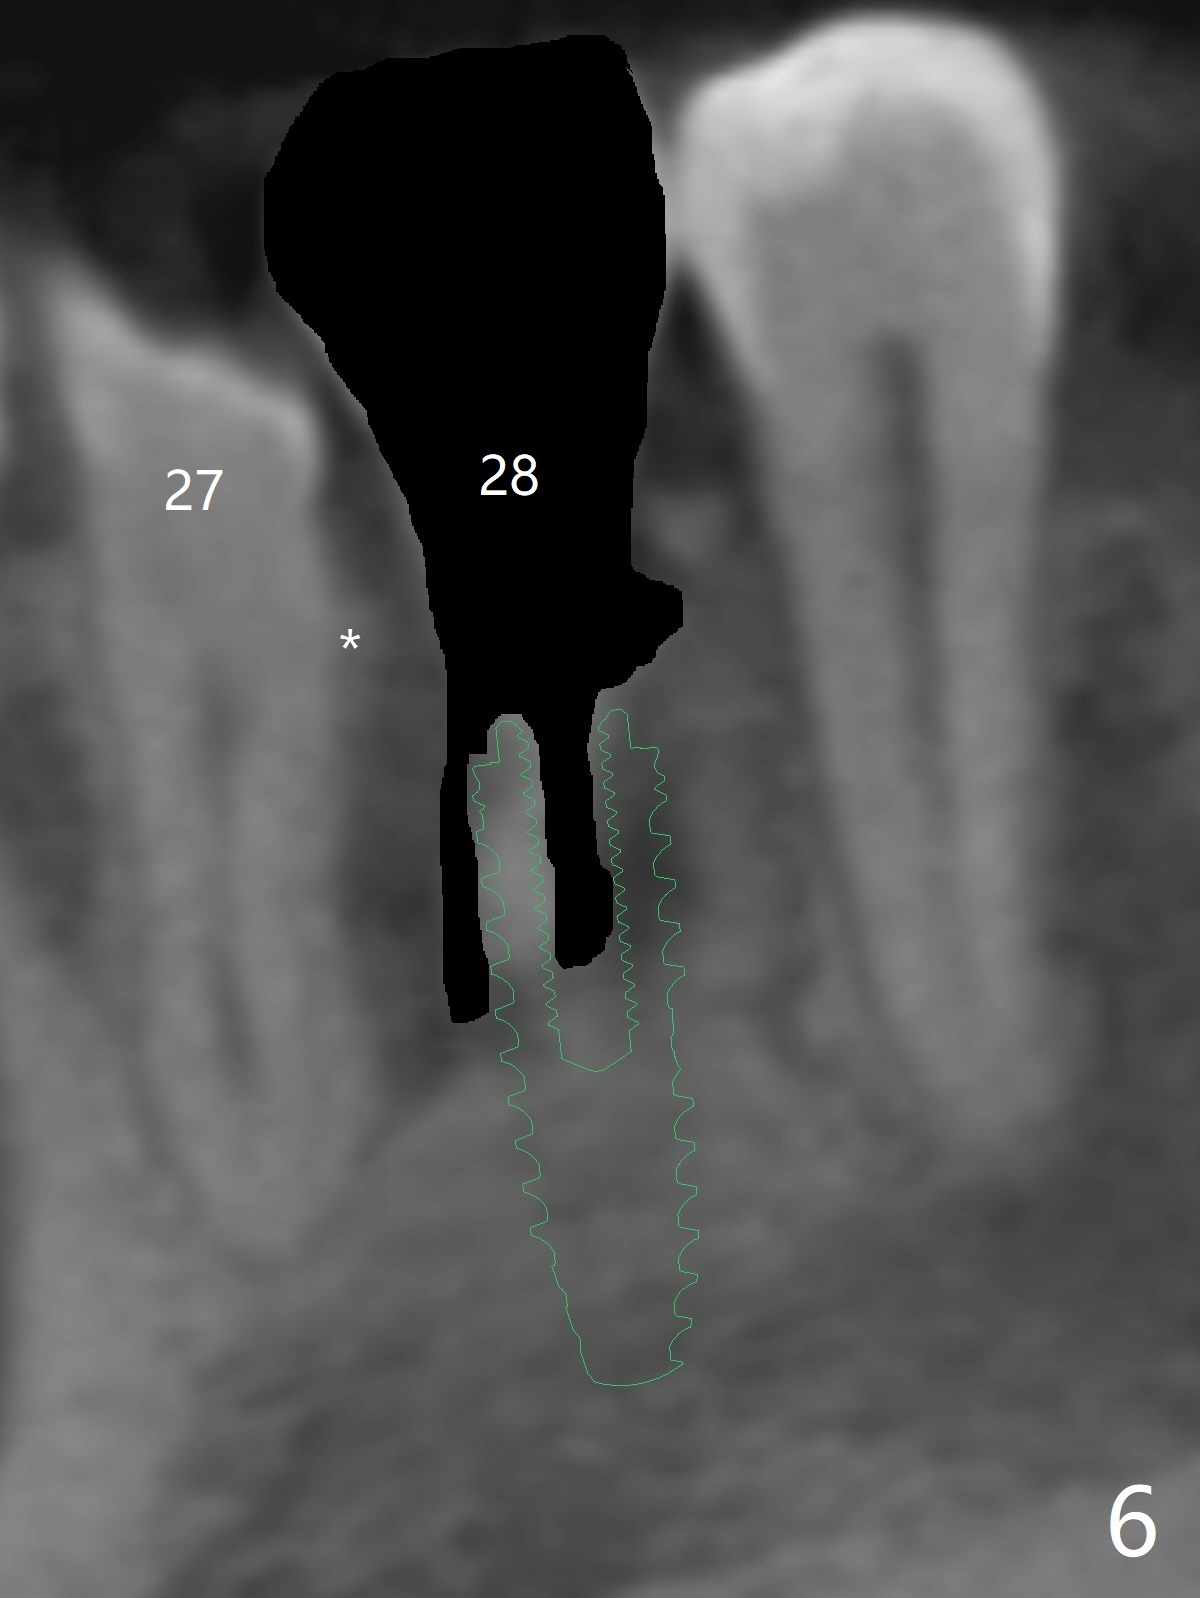

A -year-old man seeks treatment for the tooth #28 with severe bone loss (Fig.1 islands of bone remaining in the mesial surface of the tooth #27, reossification center for grafted bone). The tooth #28 has oblique root fracture (Fig.2 lingual view). One of treatment options is to place an immediate implant (green) at #28 as lingual as possible (Fig.3,4 (coronal section, after extraction (black area))). Sticky bone is placed buccal (Fig.5 red); some of bone graft will be pressed into the space between implant threads (arrowheads, bone and implant contact area expectedly to be higher than delayed placement due to less pressure to the native bone). In spite of severe bone loss between #27 and 28 (Fig.6 (sagittal section) after extraction), the crestal bone appears to exist in the mesial surface of #27 (*). With placement of an abutment (Fig.7 pink) and an immediate provisional (white), bone graft is packed as high as supracrestal (red). Restoration of the crest is expected to be better than socket preservation.